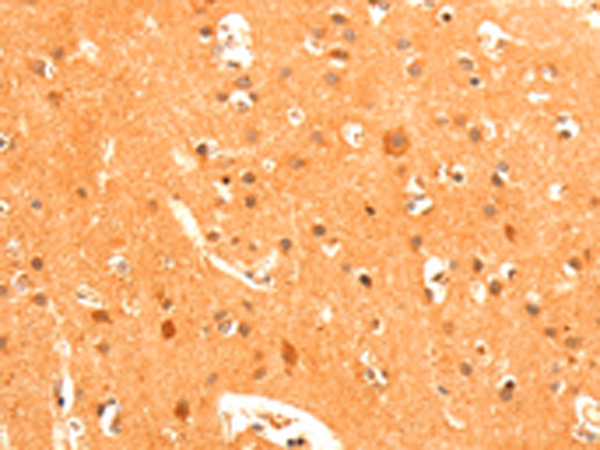

分类: 科研抗体货号: P07327别名: GLUR3; mGlu3; GPRC1C; MGLUR3应用: IHC反应种属: Human, Mouse, Rat